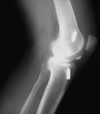

A

avulsion fracture of the fibula (arcuate fracture ) or femoral condyle